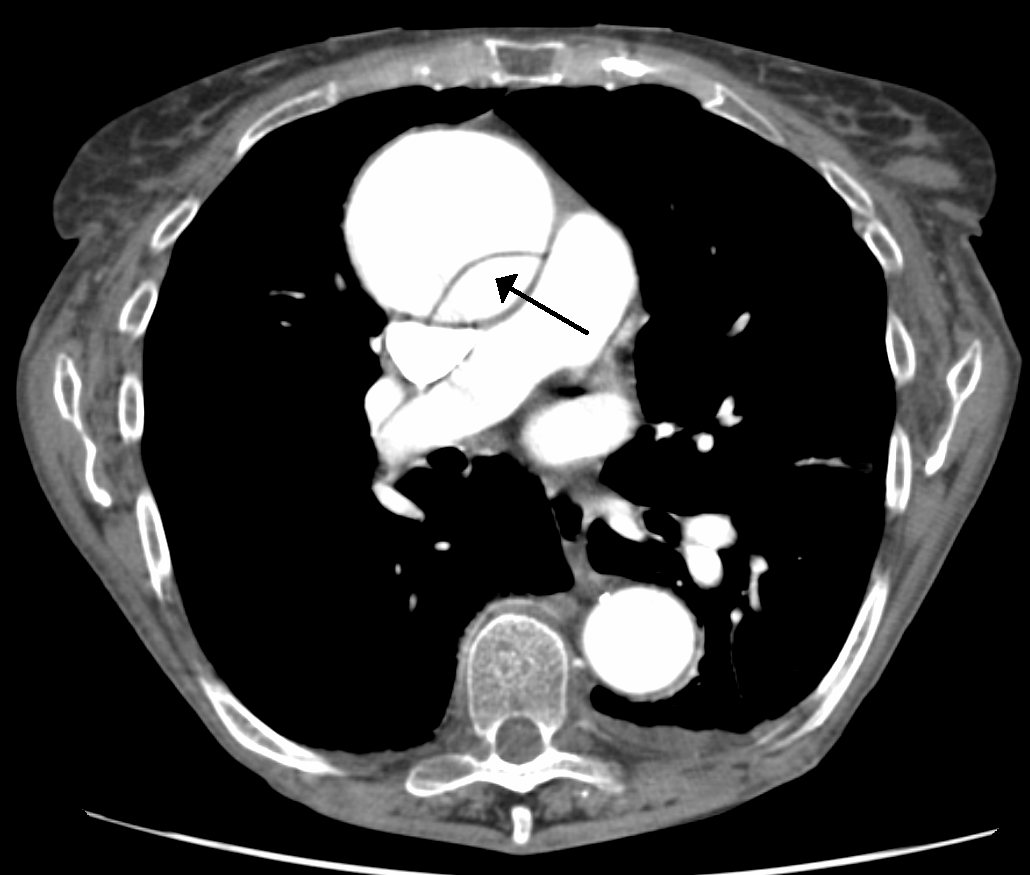

我正在研究DICOM图像(CT扫描)&想要分离出我图片中感兴趣的一些结构,比如人体器官(比如主动脉,以及所附的图像)。在ITK和VTK的帮助下,我正在C++中编码。

,我怎么能用ITK/VTK特性来保持主动脉在我的图像中呢?,我想我要找的是一个过滤器,它可以做与ITK掩模图像滤波器完全相反的事情。